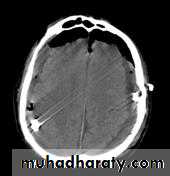

Common CT findings of traumatic brain injury